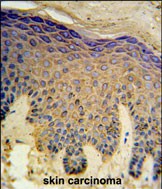

- HAUS4 Antibody (C-term) (Cat. #P30655) IHC analysis in formalin fixed and paraffin embedded skin carcinoma followed by peroxidase conjugation of the secondary antibody and DAB staining. This data demonstrates the use of the HAUS4 Antibody (C-term) for immunohistochemistry. Clinical relevance has not been evaluated.